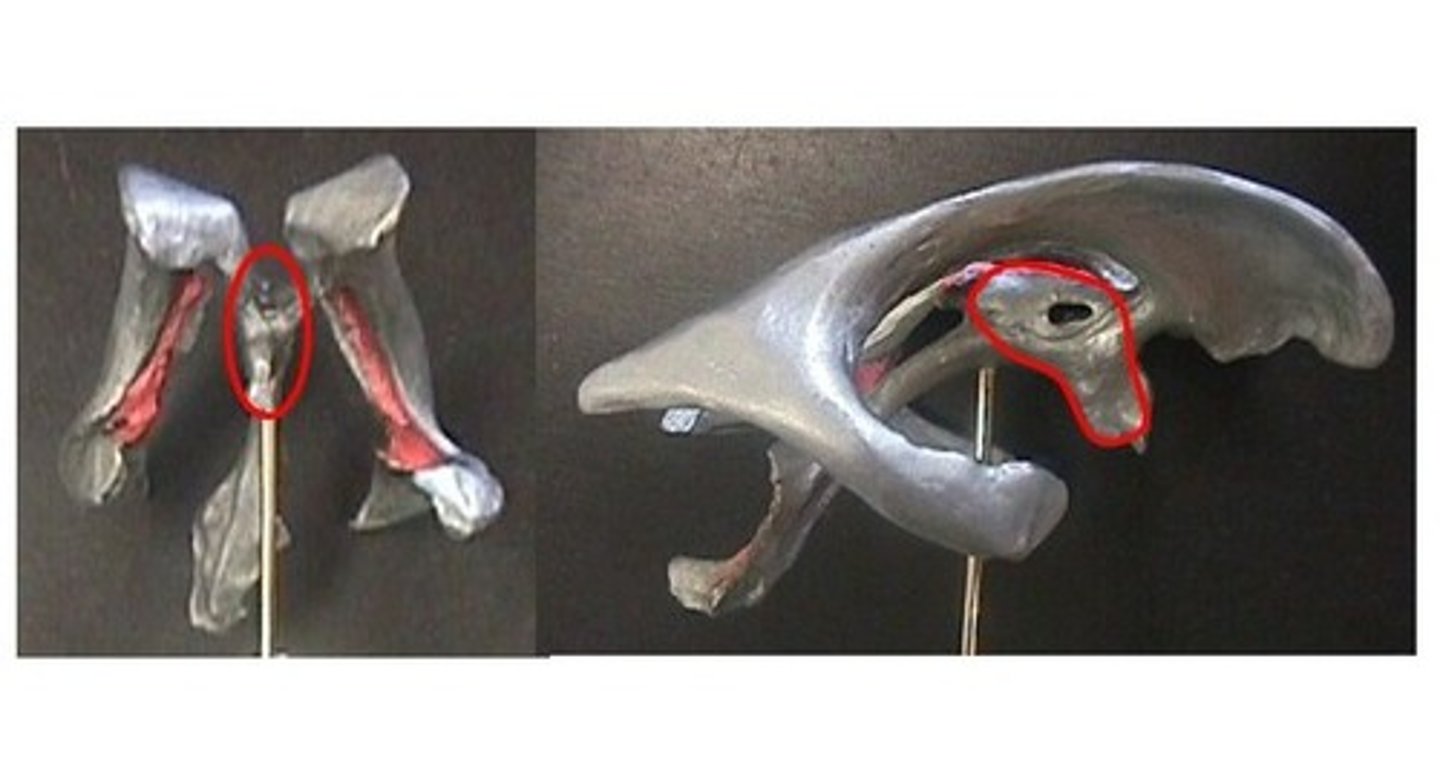

lateral ventricles

Amygdala

hippocampus